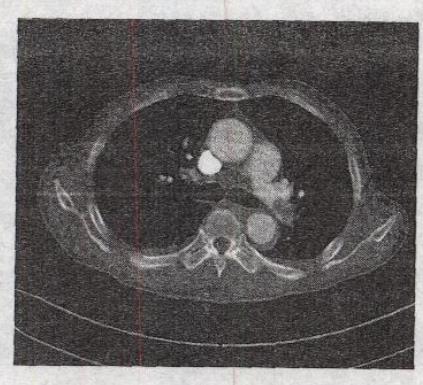

如图所示,患者发热、胸痛2个月,最可能的诊断是()。

A、肺癌

B、肺炎

C、转移癌

D、肺动脉栓塞

E、真菌感染

正确答案:

D